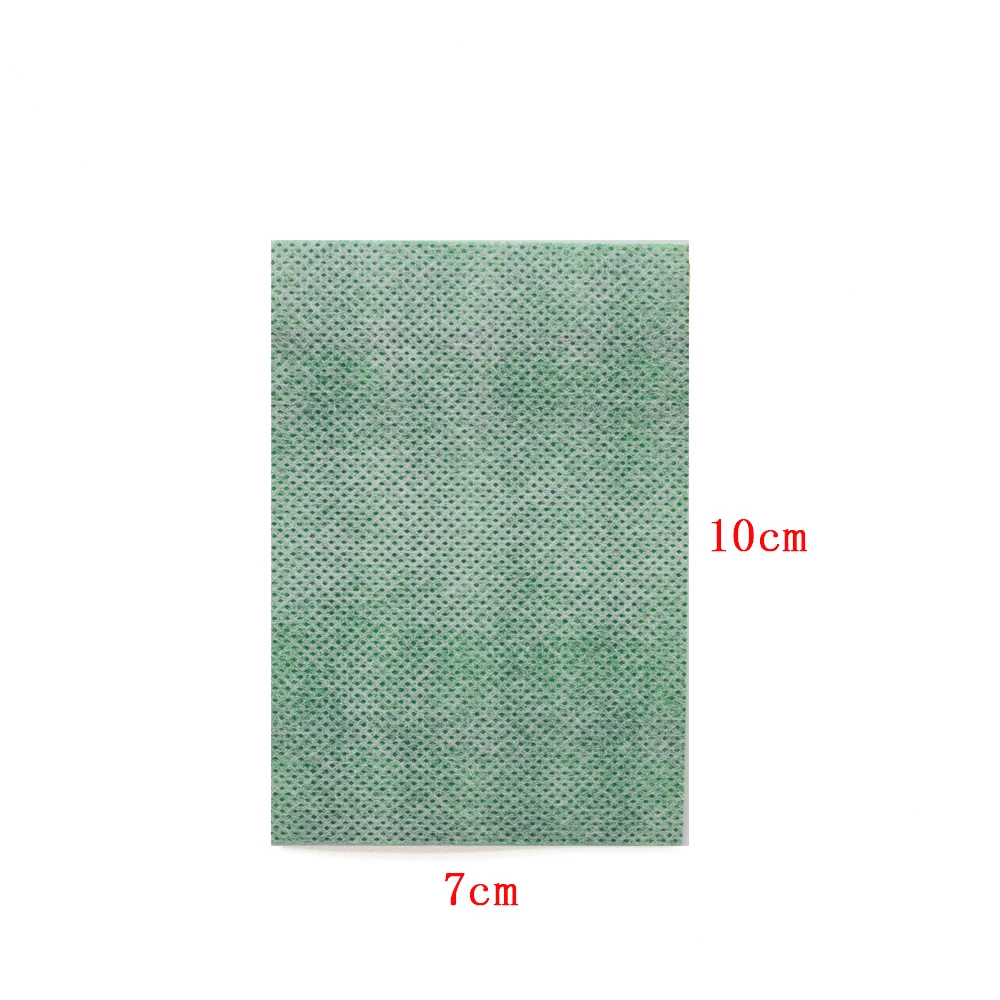

·Felxible material with Medium Size suitable for relief back muscle pain, knee joint pain, frozen neck shoulders, wrist pain, arm fatigue, rheumatoid arthritis.

·You can cut the Patch to any size you wish to fit the site of your pain!

Structure and Material:

Consist of far IR ceramic powder,medical PSA,non-woven,release paper etc.

·Felxible material with Medium Size suitable for relief back muscle pain, knee joint pain, frozen neck shoulders, wrist pain, arm fatigue, rheumatoid arthritis.

·You can cut the Patch to any size you wish to fit the site of your pain!

Structure and Material:

Consist of far IR ceramic powder,medical PSA,non-woven,release paper etc.